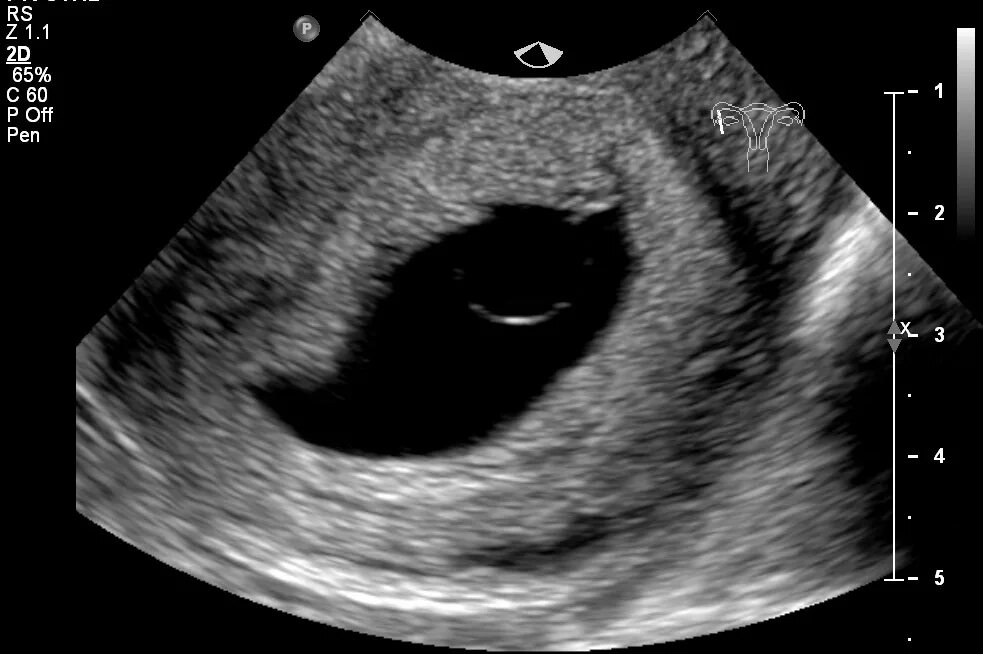

Признаки угрозы выкидыша на раннем сроке